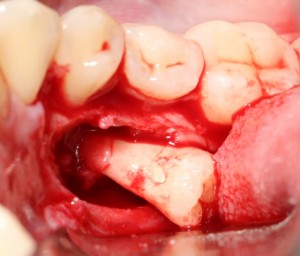

Однако, наши сверхкомплектные зубы вываливаться не хотят. Потому что их коронки образуют что-то вроде клина, который непросто вытащить через маленькое трепанационное отверстие.

Поэтому мы, всё также, с помощью ультразвука, отпиливаем коронку одного из зубов:

После чего, зубы вываливаются из лунок самостоятельно. В прямом смысле слова:

Вот удаленные зубы:

А вот их лунки:

Теоретически, лунки можно чем-нибудь заполнить. Только чем? И для чего?

Костная ткань сама регенерирует, если ей не мешать. Поэтому не стоит толкать в лунки какой-нибудь остеопластический материал, типа Cerabone или Bioss. Нет смысла.

В данном случае я использовал обычную коллагеновую губку — и то, только для того, чтобы «костная дверца», которую я выпилил в самом начале операции, не провалилась внутрь: